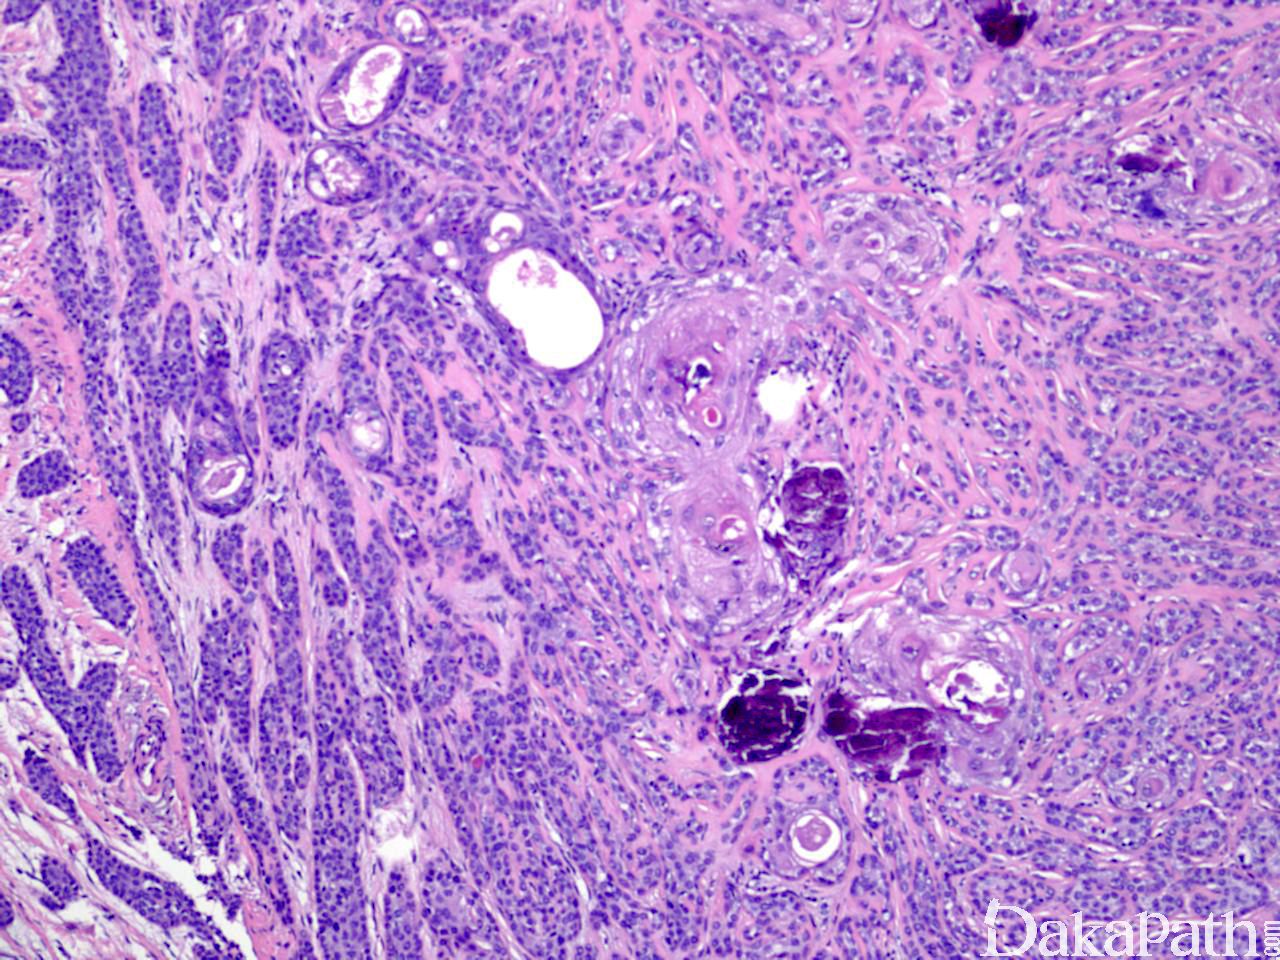

汗管癌

Syringocarcinoma

诊断要点:

局部具有汗管瘤形态学特征,但呈浸润性生长,细胞明显异型,核分裂像多见。